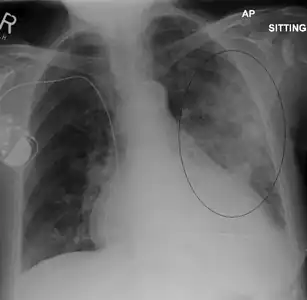

AP CXR showing left lower lobe pneumonia associated with a small left sided pleural effusion -

AP CXR showing right lower lobe pneumonia -

AP CXR showing pneumonia of the lingula of the left lung -

Right upper lobe pneumonia as marked by the circle. -

Left upper lobe pneumonia with a small pleural effusion.